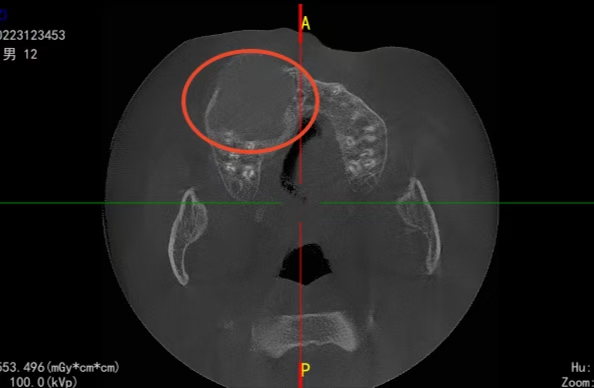

12岁孩子,巨大囊肿导致颜面变形。

现在家长的心🉑真大,12岁的小孩,外面脸和右侧鼻孔都变形了,囊肿占位面积这么大,哎~还不着急,太没意识了,看的我都着急的不行